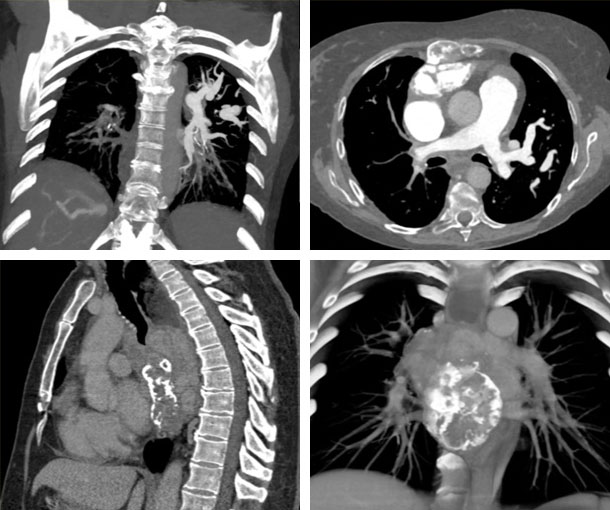

Chest CT Appearances

Fibrosing Mediastinitis CT Findings

- Mediastinal widening

- Infiltrative soft tissue

- Enlarged lymph nodes

- Tracheal narrowing

- Narrowing of the bronchi

- Can encase the pulmonary arteries

- Granulomatous (“focal”):

- Focal, localized mass

- Dense calcification

- Encapsulated

- Non-granulomatous (“diffuse”):

- Diffuse infiltration

- Does not calcify

- Less common